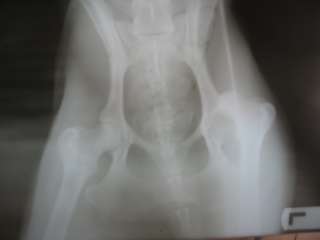

| Rasse: | Galga | Geboren: | 2008 |

Man muss Angelie lediglich beim Rennen noch ein wenig bremsen, damit sie es mit ihrem Beinchen nicht übertreibt. Mit unseren 5 Katzen und den 4 Schopfhunden kommt sie mittlerweile auch gut aus. Sie möchte aber immer "Chefin" von allen sein (auch von mir)!